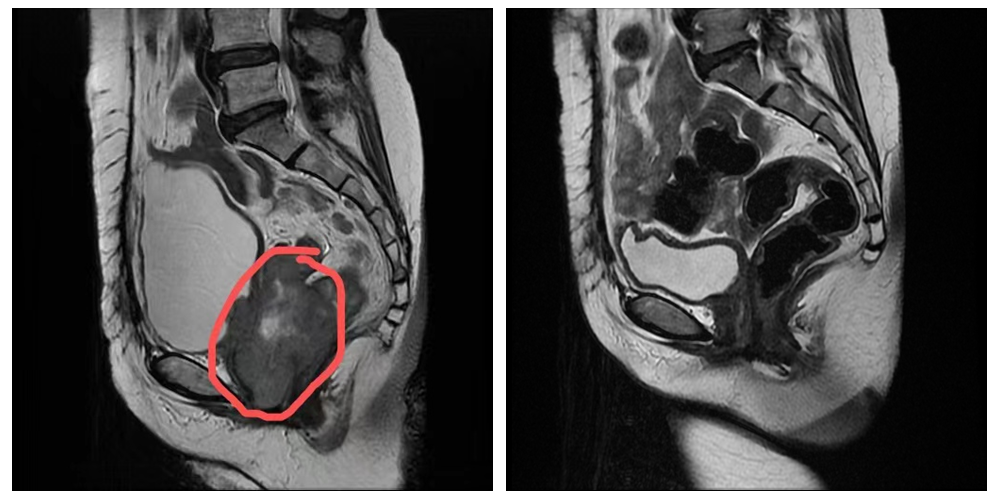

肿瘤在红圈中所示:

治疗前盆腔磁共振及复查盆腔磁共振:肿瘤已消失

患者郭某,于2020年7月在广州某大医院行宫颈癌根治术,术后患者拒绝行辅助放化疗,在家休养。2021年7月初患者开始出现下腹部疼痛不适,就诊我科门诊行盆腔增强MRI检查:宫颈癌术后复查,宫颈区见团块状肿块(范围约72mm×51mm×55mm);下腹部、盆腔见多发结节状异常信号影,较大者约27mm×22mm。建议患者入院进一步检查及治疗。患者家属经过一周考虑后,联系我科住院进一步治疗。

入院后完善检查最终诊断:宫颈癌术后局部复发IV期;下腹部、盆腔多发淋巴结转移瘤。考虑患者为宫颈癌术后局部复发,肿瘤已经侵犯阴道、膀胱三角区、左侧输尿管下段、直肠下段前壁,目前再次手术困难。经肿瘤科团队疑难病例讨论后,决定暂行诱导化疗,待肿瘤缩小后行根治性放疗。于2021年8月4日开始在我科行2程以铂类为基础的联合化疗。之后患者腹痛消失,2021年9月26日复查盆腔增强磁共振,宫颈癌术后复查:原宫颈肿块及盆腔多发淋巴结转移瘤已不可见。疗效评估达到CR(临床完全缓解)。